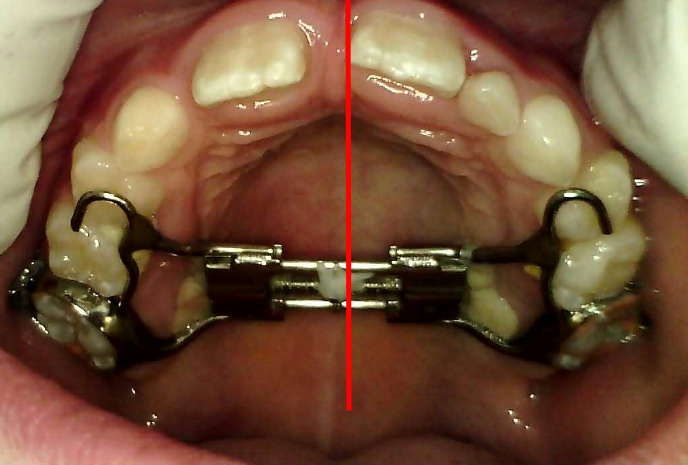

Rapid Maxillary Expansion (RME)

What It Is:

The RME appliance is a fixed device used to widen the upper jaw. When the maxilla (upper jaw) is too narrow, it can cause issues like crossbites and crowding. The RME gently and gradually opens the midpalatal suture (the joint in the center of the palate), allowing new bone to form and the jaw to widen.

How It Works:

- Activation: A small screw is embedded in the appliance and is turned at regular intervals, applying gentle pressure.

- Result: This gradual expansion creates more space for the teeth, improves bite alignment, and can lead to a more harmonious facial appearance.

- Who Benefits: Children and young adolescents who show signs of a narrow upper jaw often benefit from RME, setting the stage for smoother future dental development.